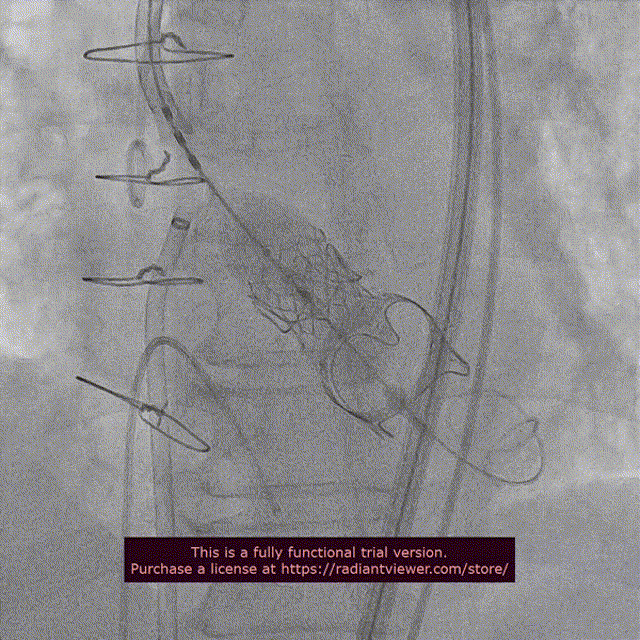

近日,中国医学科学院阜外医院潘湘斌教授团队,在多科室的通力配合下,凭借扎实的手术功底顺利完成一例经导管主动脉瓣和二尖瓣瓣中瓣置换术。

手术过程